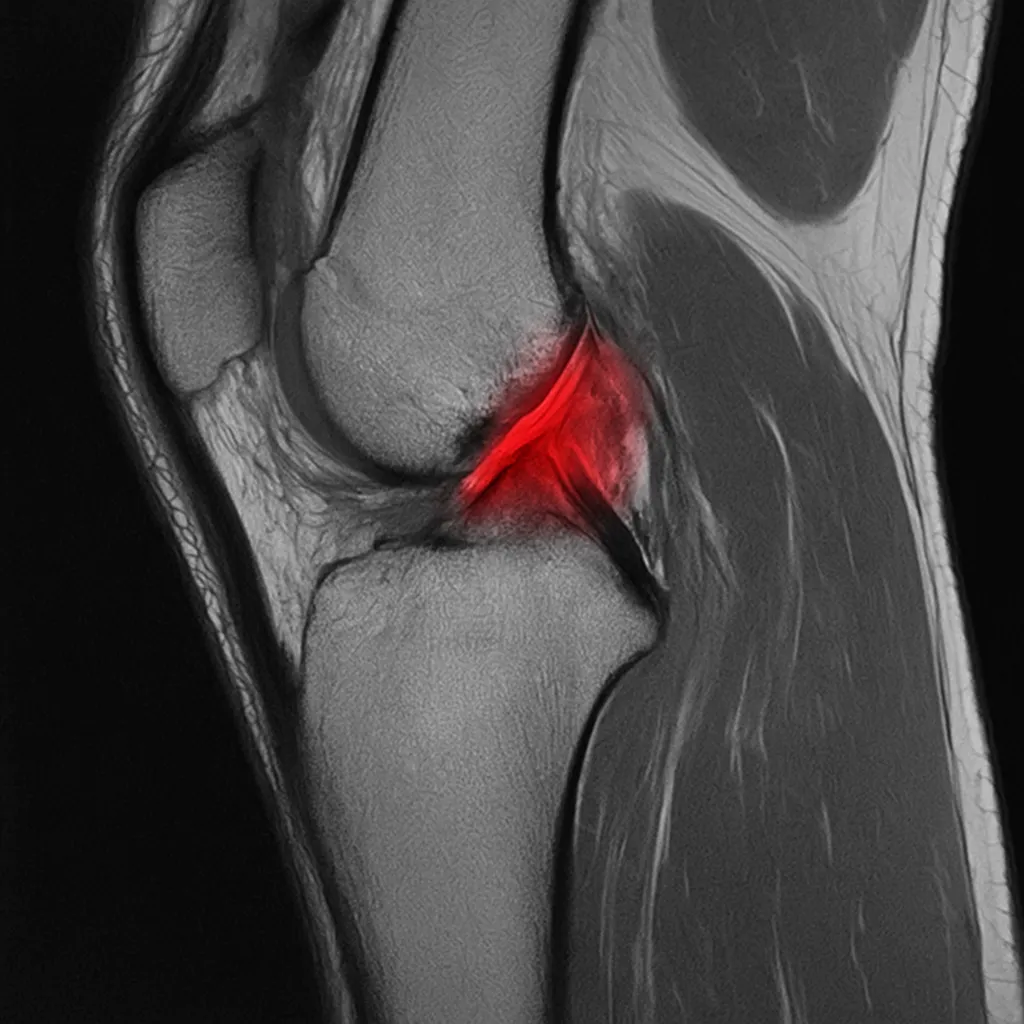

3. Képalkotás

- Röntgen: kizárja a csontsérülést.

- MRI: az arany standard, pontosan ábrázolja az ACL szakadását és az esetleges társuló meniscus- vagy porcérintettséget.